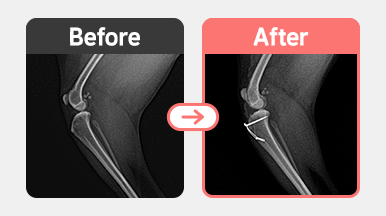

진단명 : 양측 슬개골 탈구 / 우측 G2 좌측 G3

좌측 3기 : 대퇴고랑성형 + 경골조면 이식 + 외측관절낭 부분절제

좌측은 탈구가 더 심하고 관절낭 긴장도가 낮아져 있어

홈 성형 + TTT에 더해 외측관절낭 부분절제까지 시행하여 안정성을 강화했습니다.

수술 후 양측 슬개골 정복 상태는 안정적으로 유지되고 있으며,